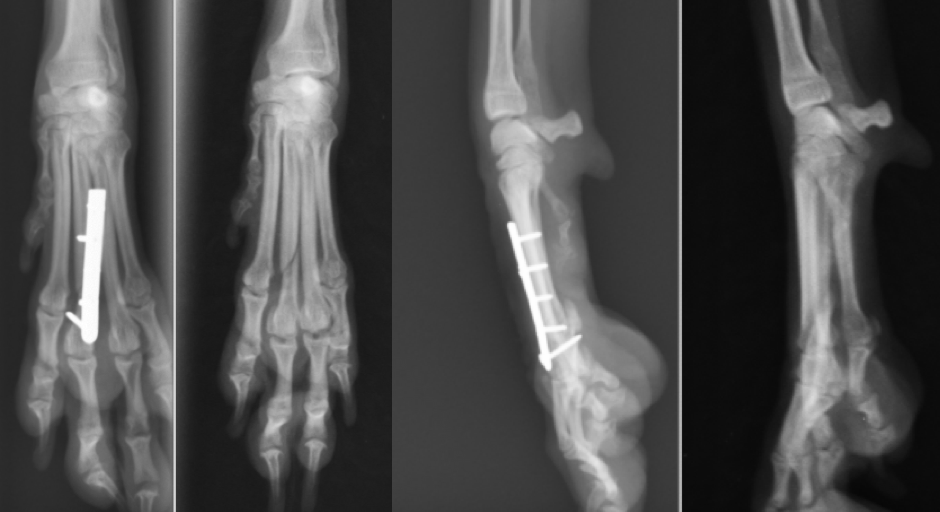

第4指の骨折です。かなり細い骨ですが、1.1mmのプレートスクリューを使用しています。